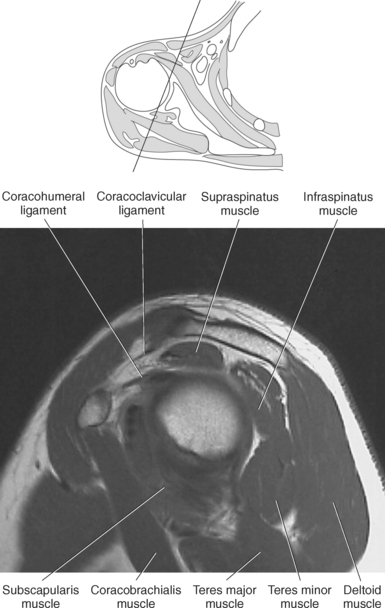

Muscles of the scapula are described in Table 9.2 and demonstrated in Figures 9.34 through 9.52. The large deltoid muscle originates on the clavicle, acromion, and scapular spine to blanket the shoulder joint as it extends to insert on the deltoid tuberosity of the humerus. This powerful muscle forms the rounded contour of the shoulder and functions primarily to abduct the arm (Figure 9.48). The teres major muscle is a flat rectangular muscle that adducts and medially rotates the arm. It extends from the inferior angle of the scapula to the medial aspect or lip of the intertubercular groove of the humerus (Figure 9.49, A). The four remaining muscles, supraspinatus, infraspinatus, teres minor, and subscapularis, closely surround the scapula and compose the rotator cuff (Figures 9.49 through 9.52). The rotator cuff provides dynamic stability to the shoulder joint and allows for adduction, abduction, and rotation of the humerus. The supraspinatus, infraspinatus, and teres minor muscles are located on the posterior aspect of the scapula. The tendons of these muscles insert on the greater tubercle of the humerus. The supraspinatus muscle lies in the supraspinous fossa of the scapula and helps to abduct the arm. The tendon of the supraspinatus muscle is the most frequently injured tendon of the rotator cuff because of possible impingement as it extends under the acromioclavicular joint and continues over the humeral head (Figure 9.49, B). The infraspinatus muscle is a triangular muscle that lies below the scapular spine in the infraspinous fossa. It acts to laterally rotate the arm (Figure 9.49, A). Lying along the inferior border of the infraspinatus muscle is the elongated teres minor muscle, which also acts to laterally rotate the arm (Figure 9.49, B). The subscapularis muscle is the only muscle of the rotator cuff located on the anterior surface of the scapula; its tendon inserts on the lesser tubercle of the humerus (Figures 9.50 through 9.52). The subscapularis muscle acts to medially rotate the humerus. See sequential images through the shoulder (Figures 9.34 through 9.47).

The edge of the glenoid fossa is surrounded by a fibrocartilaginous ring termed the glenoid labrum (glenoid lip) (Figure 9.17). The glenoid labrum is a fold of the articular capsule, which functions to deepen the articular surface of the glenoid fossa. Superiorly, the labrum blends with the long head of the biceps brachii muscle. In cross section it appears triangular (Figure 9.18). The three glenohumeral ligaments (superior middle, and inferior) are thickenings of the fibrous capsule that surrounds the shoulder joint; they contributes to the formation of the glenoid labrum (Figures 9.17 and 9.19). They extend from the supraglenoid tubercle of the scapula to the lesser tubercle of the humerus. Also aiding in strengthening the fibrous capsule is the coracohumeral ligament that passes from the lateral side of the coracoid process of the scapula to the anatomic neck of the humerus (Figure 9.19). The coracoacromial ligament is another important ligament located on the anterior portion of the shoulder. As this ligament joins the coracoid process and acromion, it forms a strong bridge, termed the coracoacromial arch, which protects the humeral head and rotator cuff tendons from direct trauma and prevents displacement of the humeral head superiorly (Figures 9.17 and 9.19). The coracoclavicular ligaments help to maintain the position of the clavicle, in relation to the acromion, by spanning the distance between the clavicle and coracoid process of the scapula (Figure 9.19). The acromioclavicular ligament, at the acromioclavicular joint, provides support for the superior surface of the shoulder (Figures 9.17 and 9.19). The transverse humeral ligament is a broad band of connective tissue passing from the greater tubercle to the lesser tubercle of the humerus, forming a bridge over the intertubercular groove for protection of the long head of the biceps tendon (Figure 9.19). The ligaments of the shoulder are demonstrated in Figures 9.20 through 9.30.